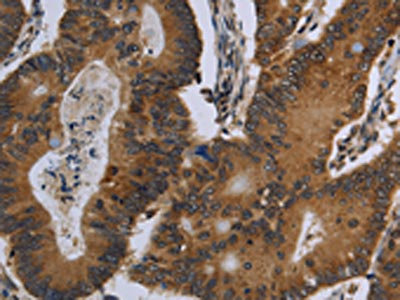

The image on the left is immunohistochemistry of paraffin-embedded Human colon cancer tissue using CSB-PA120525(FGF18 Antibody) at dilution 1/20, on the right is treated with fusion protein. (Original magnification: ×200)